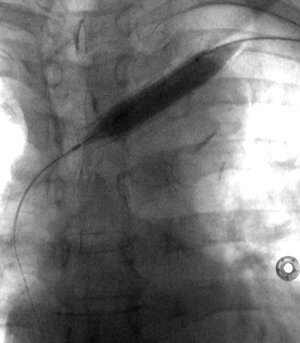

35 year old male patient with CKD requiring hemodialysis via a LUE AV graft. He presents with left upper extremity swelling secondary to a left brachiocephalic vein occlusion.

Comment: This chronic occlusion was treated with stent placement. Unfortunately, the stent occluded within months of placement, necessitating placement of additional stents. This happened again a few months later, requiring angioplasty and covered stent placement.